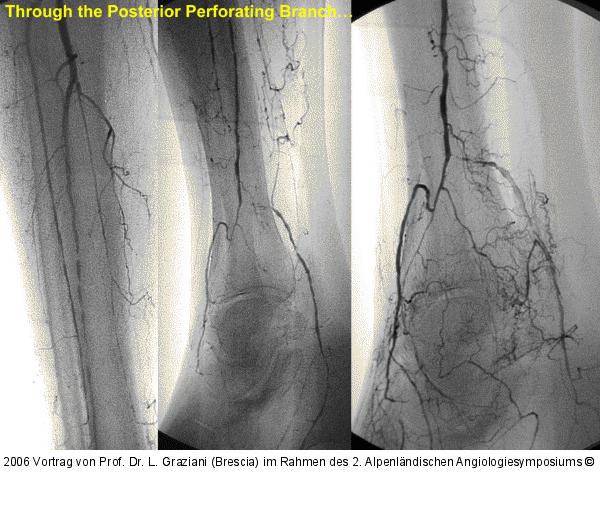

Vortrag von Prof. Dr. L. Graziani (Brescia) im Rahmen des 2. Alpenländischen Angiologiesymposiums

PTA of the foot arteries in diabetics: Extremities Extreme Angioplasty

Abbildung 60: P.O.B.A.